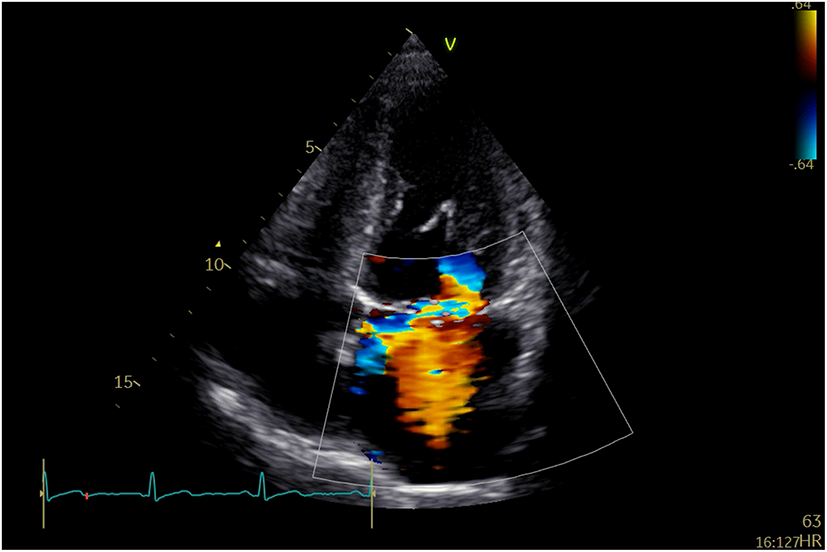

A 58-year-old man was repeatedly referred to the respiratory clinic for cough, sputum, and fever since 2003. He was founded with posterior mitral valve prolapse with mild MR in 2013. He felt palpitation and exertional dyspnea in March 2019. TTE and TEE revealed severe MR due to P1, and P2 leaflet prolapse; borderline LV cavity size with LVEF ~65%. Holter: sinus tachycardia, several episodes of supraventricular contractions, and premature ventricular contractions. On examination, his vital signs were stable (BP: 129/71 mmHg, p: 86 beats/min). He underwent Neochord mitral valve repair with 3 artificial chords, with residual trivial MR and a mean trans-mitral gradient of 2–4 mmHg. Thirty months after he was discharged from the hospital, he was admitted to the hospital again for an exertional SOB. TTE indicated severe anterior directed MR due to partially ruptured artificial chords (Figure 2).

Figure 2

TTE revealed recurrent severe MR due to partially ruptured artificial chords.